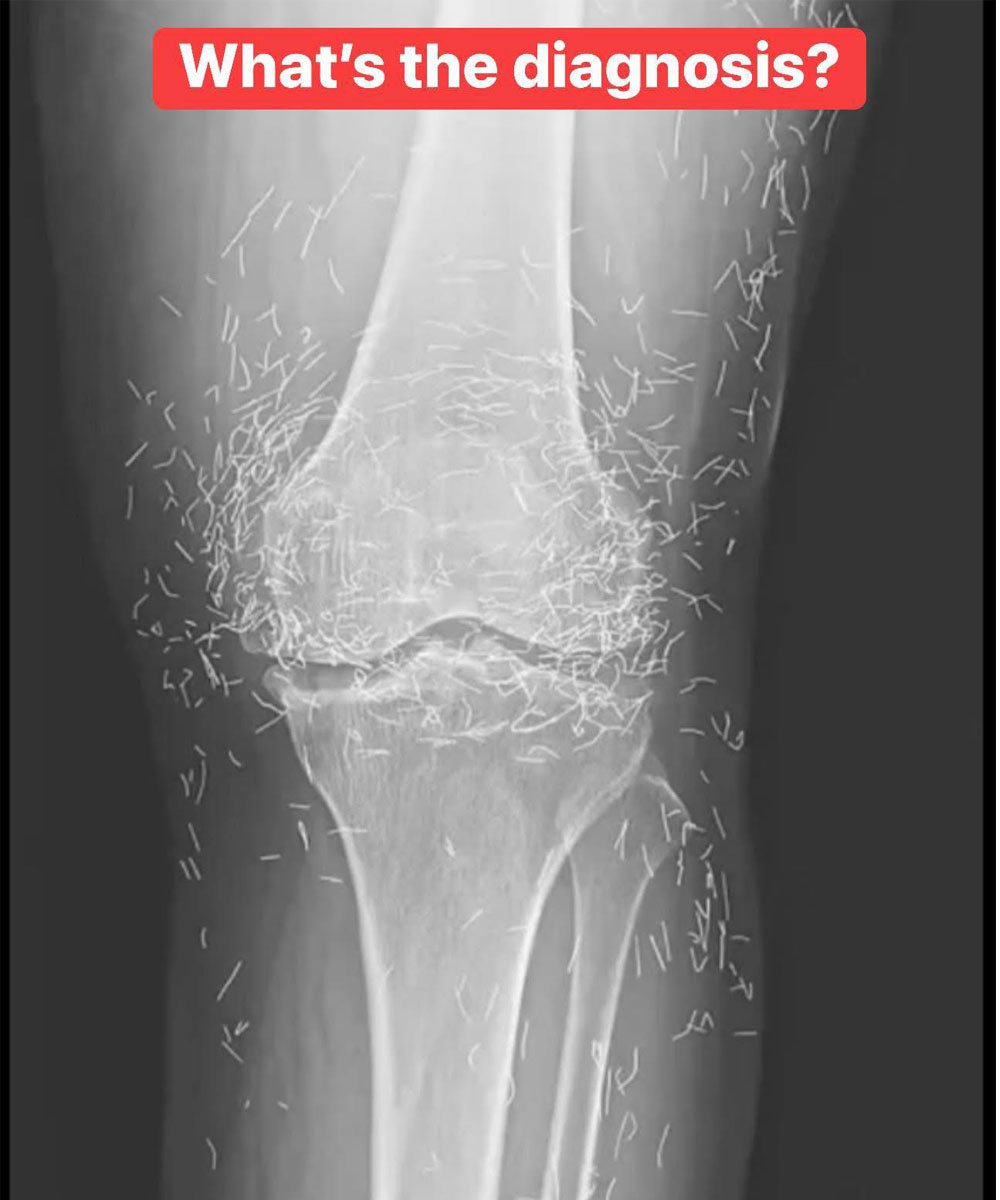

X-Ray Reveals Hundreds of Gold Needles in Woman’s Knees

As doctors examined an X-ray image of the knees of an old woman experiencing severe joint pain, they found a gold mine: hundreds of tiny gold acupuncture needles left in her tissue.

In the woman’s acupuncture treatment, the needles, which were presumably made of gold, were intentionally left in her tissue for continued stimulation, the report says.